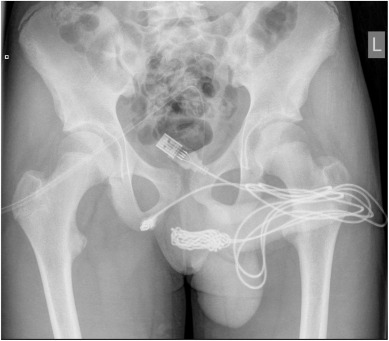

Un curioso adolescente de 15 años fue hospitalizado después de insertar un objeto inusual en su pene con la intención de medir su longitud, según un nuevo informe médico. El chico, residente del Reino Unido, se presentó en el servicio de emergencias de su hospital local con un extraño problema: un cable USB enredado insertado en su uretra, que además de ser doloroso, le había causado una considerable pérdida de sangre en su orina después de intentar sacarlo.

Los médicos descubrieron que los extremos del cable USB estaban sobresaliendo del meato urinario externo, mientras que la parte media del cable estaba enredada en la uretra del adolescente. Una vez que su madre se retiró de la habitación, el joven confesó a los médicos que había insertado el cable en su uretra para medir su miembro. Su curiosidad sexual lo llevó a elegir un cable en lugar de una regla externa.

El equipo médico intentó remover el cable a través de una cistoscopia rígida y una uretrotomía óptica, pero ambos intentos fallaron debido al enredo. Por lo tanto, se necesitó cirugía para extraer el objeto extraño.

En términos más simples, los médicos hicieron una incisión penoescrotal longitudinal y realizaron una disección cuidadosa para extraer el cable del adolescente. Los extremos del cable se retiraron con éxito a través del meato urinario externo, y el paciente se recuperó bien después de la cirugía.